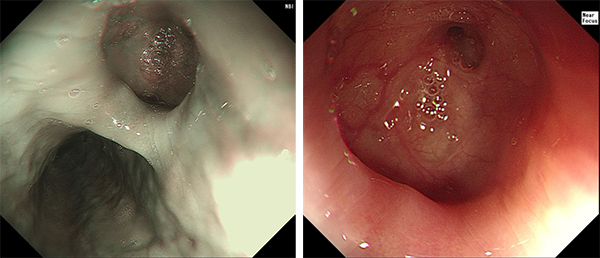

在呼吸科的积极治疗下,李大娘的肺部感染很快得到控制,消化内镜中心第一时间为李大娘安排了胃镜检查,在内镜进入食管中下段的一瞬间,李大娘多年咳嗽的原因就立刻“跃然镜上”了。在食管距门齿32公分的位置,可以看到一处食管憩室,也就是李大娘女儿说的“囊”,就像一个气球的薄弱部位,当充气或充水的时候,憩室就会向外凸起。而在这个憩室的顶端,可以看到一处约2mm的圆形小瘘口,所以我推测,在上次胃镜检查后的某一次用力咳嗽或进食硬食的瞬间,薄弱的憩室壁破裂,形成了食管瘘,这个瘘口可能通向支气管,进食后食物通过瘘口进入呼吸道,造成呛咳、肺部感染。由于瘘口较小,成型的食物不易通过,而水或流食则容易顺着瘘口流入支气管。